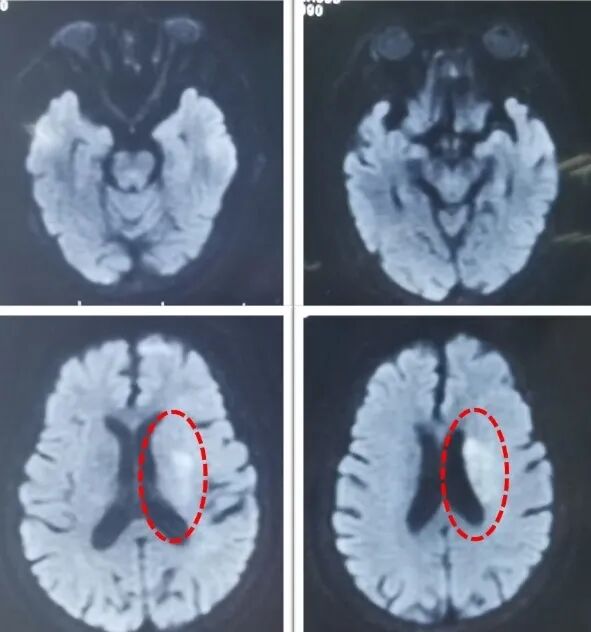

头颅MRI示:左侧基底节区及侧脑室旁新新鲜梗死灶,左侧颈总动脉闭塞。

图2:头颅DWI提示左侧侧脑室旁基底节区新鲜脑梗死;

术后3天DWI:左侧大脑半球额颞顶叶多发散在新鲜梗死灶。

术后3T天ADC: